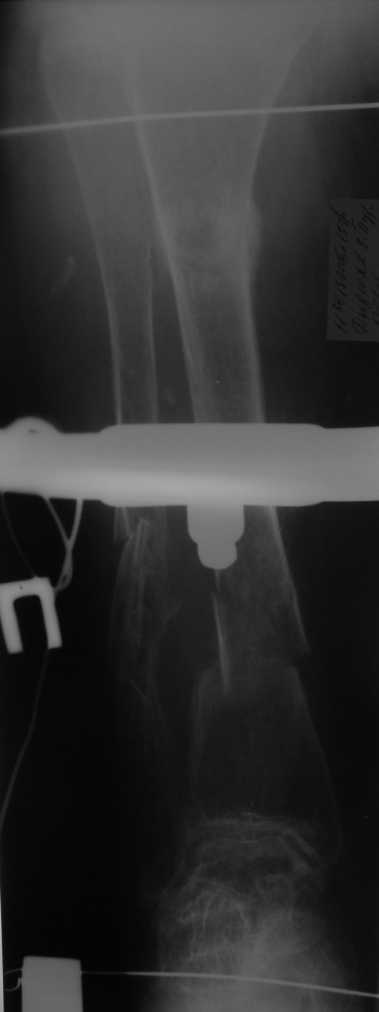

Уважаемые коллеги! Здравствуйте! Прошу у Вас совета вот по какому случаю.В нашу клинику поступила женщина 71 год. Травма в результате ДТП. (Пациентка передвигалась на инвалидной каляске и была сбита автомобилем). Диагноз: Множественная травма. Перелом нижней трети правого бедра. Перелом средней трети правой б/берцовой, малоберцовой кости, нижней трети левой большоберцовой, м/берцовой кости.Травматический шок. Со стороны внутренних органов и систем без патологии. Больная госпитализирована в реанимационное отделение, где было наложено двойное скелетное вытяжение за правую н/конечность. Левая н/конечность иммобилизована гипсовой лонгетой. Из анамнеза: больная является инвалидом 1 группы по опорно-двигательному аппарату. В детстве перенесла рахит. Осложнением которого "О" образная деформация нижних конечностей. Ограничено отведение нижних конечностей, деформирующий артроз тазобедренных и коленных суставов. В 1990 году перелом правого бедра остеосинтез пластиной. После операции больная передвигалась только на костылях или в инвалидной коляске.

Прошу прощения за качество снимков. Р-графия производилась в реанимационном отделении передвижным аппаратом.

Но даже при малоинвазивной методике лечения применимой для даной больной существуют следующие проблемы: выраженный остеопороз, тонкий кортикал, очень широкий канал.

Контрольные рентгенограммы прилагаю.

Проблема в том, что в сагитальной плоскости угол голеней =30 градусам. Ширина канала 30.